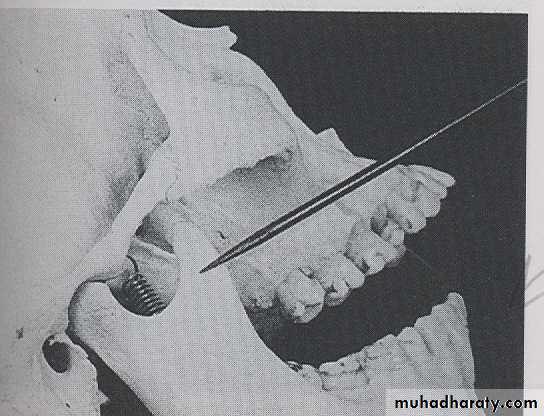

CORONOID PROCESS:

The coronoid process is a marked prominence of bone on the anterior ramus of mandible. Radiographically the coronoid process is not seen on mandibular periapical radiography but dose appears on maxillary periapical film as triangular radiopacity superimposed over the maxillary tuberosity region.